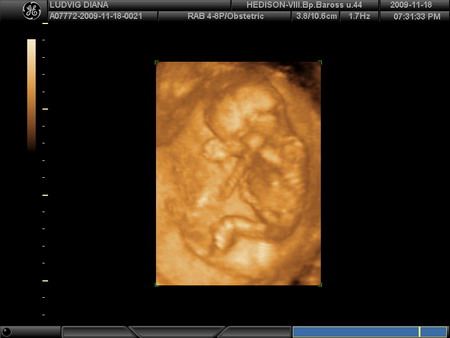

Kis Tündérkénk 27 hetesen és 1 naposan:

Kép Kép Kép Kép